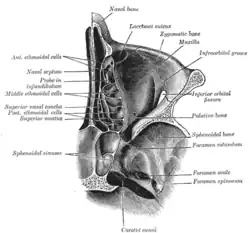

O crânio da frente. Seção horizontal das cavidades nasais e orbitárias.

Seção horizontal das cavidades nasais e orbitárias. Óculos orbicular esquerdo, visto por trás.